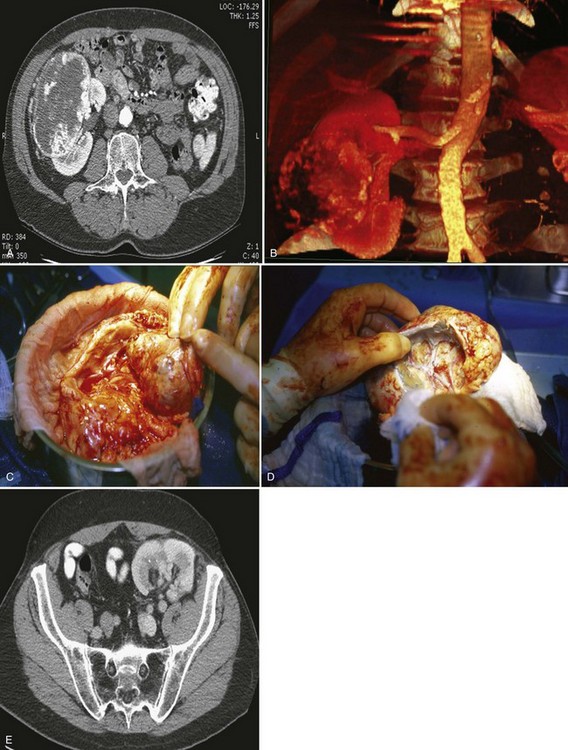

Three-dimensional (3D) volume-rendered CT is a valuable tool in the evaluation of patients undergoing renal surgery (Coll et al, 1999; Derweesh et al, 2003). CT can demonstrate vital information including the anatomy of the renal vasculature, orientation of the kidney, and characteristics of renal tumors, including location, depth of penetration into the kidney, relationship with collecting system, and segmental arterial supply to the tumor (Coll et al, 1999) (Figs. 54-12 to 54-14). CT is also able to characterize other surgically relevant processes, including renal arterial disease, nephrolithiasis, and hydroureteronephrosis (Herts, 2005).

Figure 54–12 Contrast-enhanced CT axial reconstruction demonstrating large right hypervascular mass suggestive of renal cell carcinoma.

Figure 54–13 CT scan demonstrating two incidentalomas in an elderly man undergoing imaging to rule out appendicitis. A left partial nephrectomy was performed first followed by a right radical nephrectomy in 3 to 4 months.

Figure 54–14 A, Preoperative imaging demonstrates a large 4-cm hilar lesion during a noncontrast film in a patient with a history of von Hippel-Lindau disease. B, Contrast administration demonstrates enhancement of a large intrarenal mass and nearby simple cyst. C, Delayed images depict close proximity to collecting system.

The importance of imaging to open renal surgery is likely to increase with time. Future possibilities include image-guided open surgery, the objective of which is to provide surgeons enhanced visualization of the surgical field by merging data from preoperative images with an intraoperative view (Benincasa et al, 2008). In addition, simulation of complex nephron-sparing surgery based on 3D imaging may be possible (Wunderlich et al, 2000).

Proposed benefits of preoperative RAE include shrinkage of an arterialized tumor thrombus to ease surgical removal, reduced blood loss, facilitation of dissection due to tissue plane edema, ability to ligate the renal vein before the renal artery at time of nephrectomy, and modulation of the immune response (Klimberg et al, 1985; Bakal et al, 1993; Kalman and Varenhorst, 1999; Schwartz et al, 2007; Wotkowicz and Libertino, 2007; Wszolek et al, 2008). Ligation of the renal vein before the renal artery is useful in the setting of hilar tumors, tumors with significant medial extension, or considerable perihilar adenopathy (Schwartz et al, 2007; Wotkowicz and Libertino, 2007; Wszolek et al, 2008). Before ligating the renal vein, one should characterize the completeness of embolization to prevent unnecessary blood loss in cases of incomplete embolization. In the senior author’s experience this assessment can be made by evaluating renal venous return during surgery. In addition, angioembolization can also be useful for renal tumors associated with large arteriovenous malformations that are having a deleterious hemodynamic impact (Figs. 54-16 and 54-17).

Figure 54–16 Noncontrast (A) and contrast-enhanced (B) CT images of a patient with high output cardiac failure secondary to arteriovenous malformation associated with left renal cell carcinoma. Notice the equal contrast intensity of the aorta, left renal artery, and left renal vein.